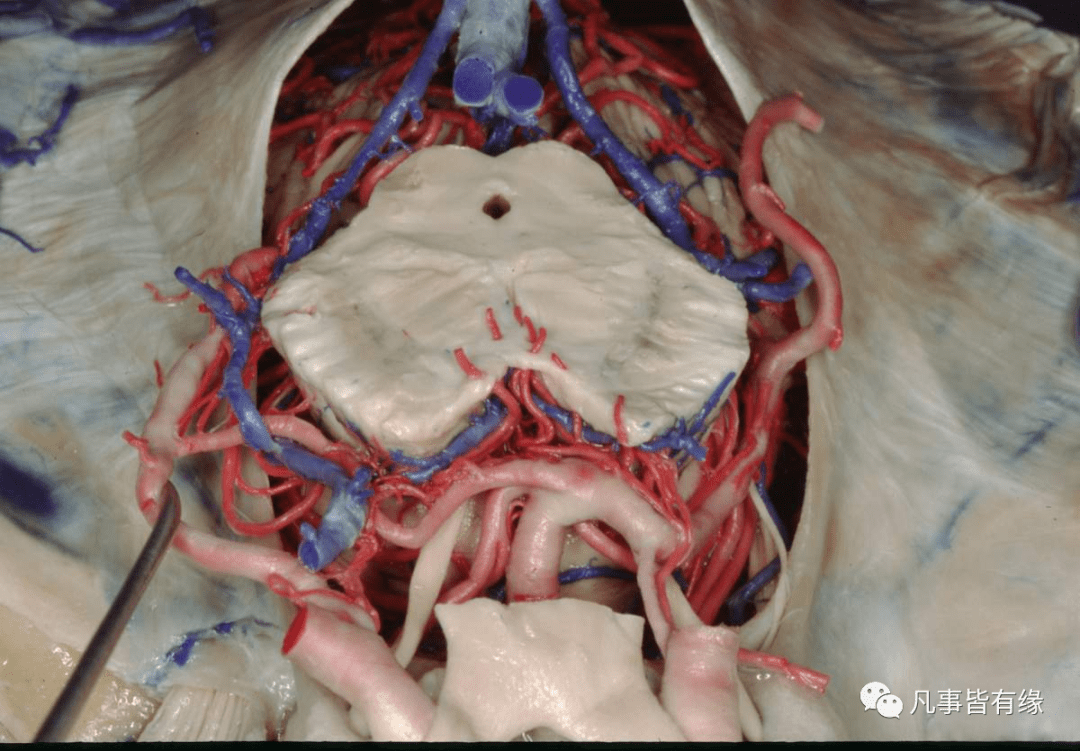

皱眉肌纹的深面是滑车上动脉

发病机制眼动脉的分支有睫状前动脉,睫状后动脉,泪腺动脉,滑车上动脉

视神经的外侧,然后在上直肌的下方越至眼眶的内侧前行,终于滑车上动脉